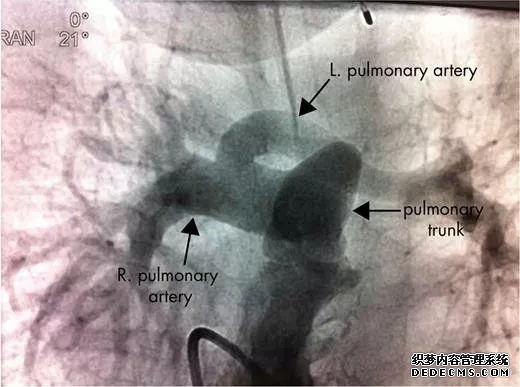

3、肺动脉造影、支气管造影创伤性较大,现很少使用;

(DSA)